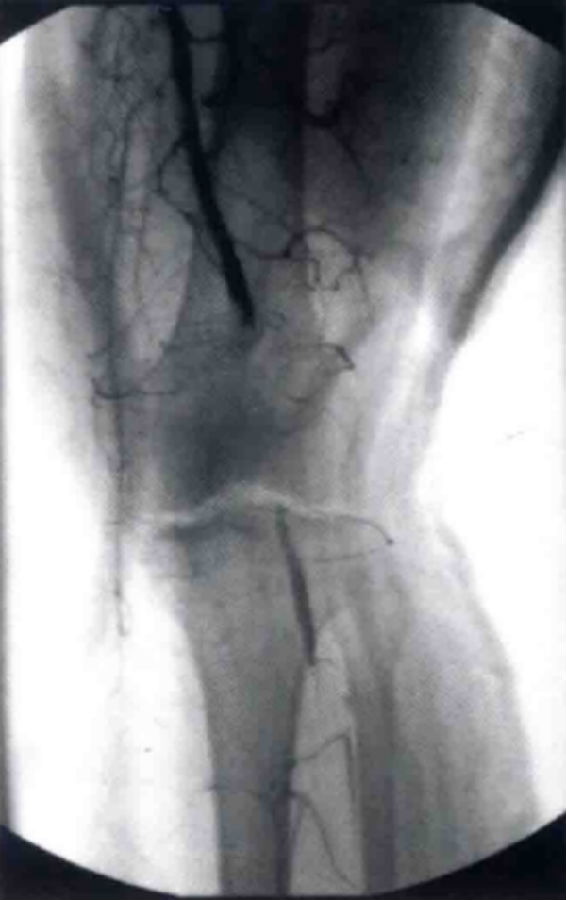

初步评估应涵盖全而的体格检查。因为膝关节脱位经常发生于多发性创伤的患者,体格检查应当包含对患者头部、胸部、腹部和四肢的一般评估。初步检查应包括检查膝关节贯穿伤口、存在的畸形以及膝关节活动度的检查。检查制带时必须包括屈膝20°时Lachman检查、屈膝90°时前后抽屉试验、屈膝0°和30°时内外翻应力试验,以及如果患者能够耐受疼痛时需行Dial试验。对膝关节脱位的检查通过采取标准的Lachman试验(将检查者的大腿置于被检者的膝关节下)通常可以减少疼痛以及提高准确性。触诊通常用于检查伸膝装置或䐃绳肌腱断裂。如患者可进行直腿抬高动作,对于伸膝装置的情况检查十分有用。另外,应仔细检查血管的解剖情况,这对于膝关节脱位的治疗方式起到决定性的作用。如果血管损害被延迟诊断,可导致骨筋膜室综合征甚至截肢。最简易的血管检查包括触诊胫后和足背动脉搏动以及毛细血管充盈时间的触诊。基于初步评估,进一步的检查应当根据循证指南进行,包括ABI指数、血管造影、血管CT造影和腘动脉紧急探查。血管治疗的必要性取决于检查的结果(图1),而神经功能检查评估对于无意识的患者或有多发创伤存在的患者十分困难,对于胫神经和腓总神经的评估十分重要,需要尽量进行。术前神经损伤的诊断可以帮助制订治疗计划和预测结果。

图1 膝关节脱位导致腘动脉损伤的血管造影图像